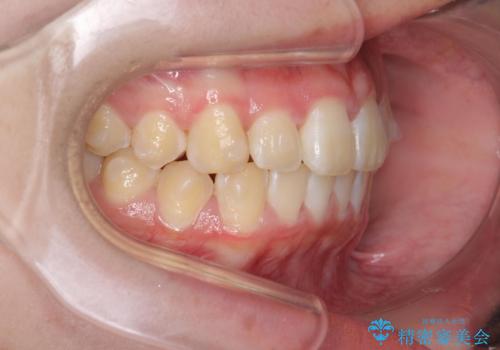

前歯のがたつき気になる。インビザラインモデレート

- 前歯のがたつきが気になるとの事で来院。

マウスピース矯正希望でしたのでインビザラインモデレートで治療を行いました。

がたつきが無くなり満足して頂けました。